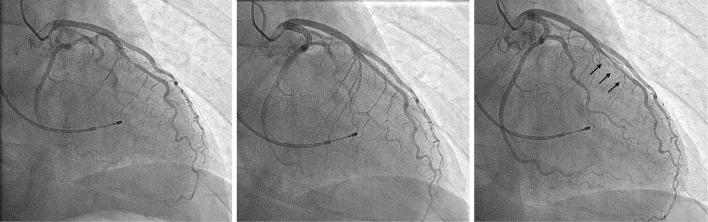

A 61-year-old man experienced chest oppression for 1 hour. He was positive for troponin T and underwent emergent coronary angiography (CAG), which did not reveal significant coronary stenosis. He was diagnosed with myocardial infarction with nonobstructive coronary arteries (MINOCA). We performed a spasm-provocation test, which revealed a focal spasm at the segment of the myocardial bridge. After receiving a calcium-channel blocker, he exhibited a good clinical course. Coronary spasm is considered an underlying cause of MINOCA; therefore, the presence of a myocardial bridge may help with the diagnosis.

一名61岁男性经历了1小时的胸部压迫感。他肌钙蛋白T呈阳性,接受了急诊冠状动脉造影(CAG),结果未显示明显的冠状动脉狭窄。他被诊断为非阻塞性冠状动脉心肌梗死(MINOCA)。我们进行了痉挛激发试验,结果显示心肌桥节段存在局灶性痉挛。在接受钙通道阻滞剂治疗后,他的临床病程良好。冠状动脉痉挛被认为是MINOCA的潜在病因;因此,心肌桥的存在可能有助于诊断。